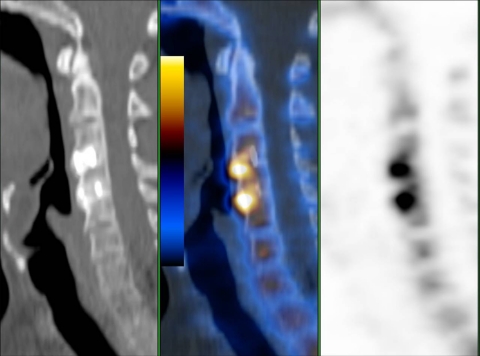

Fig. 2.

52-year-old male patient 79 months postoperatively with both cervical cages (C3/4, C4/5) showing increased uptake (patient no. 8). Sagittal low-dose CT, fused PET/CT, PET

Regarding cervical intercorporal fusions, there were four patients with more than one intervertebral fusions, three with two adjacent segments either both with or without increased uptake. One patient had received three adjacent intercorporal fusions of which only the lowest showed increased uptake (Figs. 1, 2, 3).